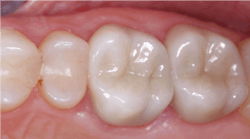

- Zirconia with stains placed on the presintered ceramic and fired into the restorations: Currently only offered by select labs; this material is looking promising (figure 2)